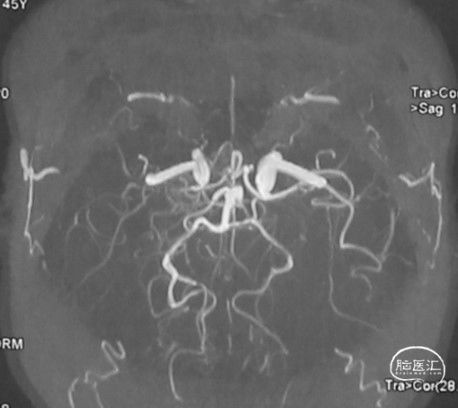

MRA:双侧大脑中动脉、左侧大脑前动脉重度狭窄至闭塞

左侧颈内动脉末段、大脑前动脉A1段、大脑中动脉M1段变细:

左侧颈内动脉正位:

左侧颈内动脉侧位: